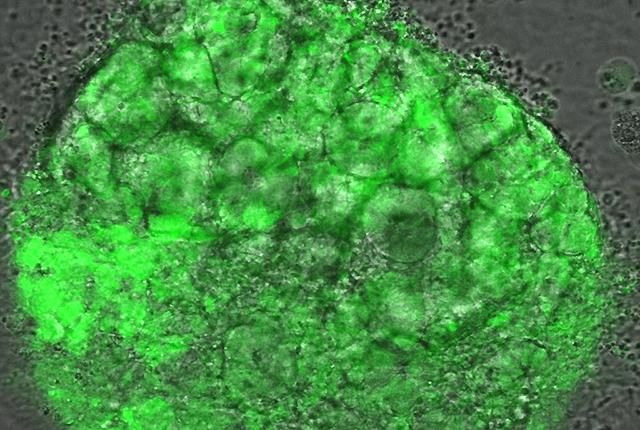

Dr. Benjamin “Beno” Freedman, a UW Medicine nephrology researcher, has been studying these injuries since last summer. He’s using organoids, complex mini-organ structures grown from stem cells, which model kidney function and can be closely monitored for changes at a cellular level.

A. Yes, because you have a little piece of human kidney structure. It looks and functions similar to kidney tissue at a rudimentary level. We can perform careful experiments to see exactly what's happening; you can watch these kidney cells under the microscope and begin to understand what is occurring in the context of COVID-19. We are using organoids as a surrogate for people.

A. One thing we found is that the organoids can be infected; infectious virus can get into cells in kidney organoid cultures and is capable of replicating under those conditions. Others have begun to report this in literature as well. And we can shed some light on which types of kidney cells appear most susceptible to COVID-19.